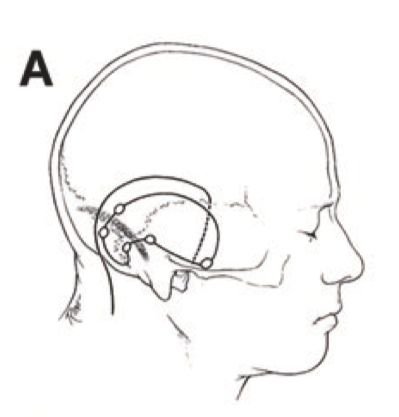

對(duì)于巖斜區(qū)腫瘤的手術(shù)理念和主張多樣,入路選擇多樣,有額顳入路,枕下小腦幕入路,顳下小腦幕入路,顳下入路,耳蝸入路等。但是對(duì)于巨大腫瘤或者同時(shí)向幕上幕下生長(zhǎng)的腫瘤,INC國(guó)際教授等分享了幕上幕下聯(lián)合入路如何成功全切,該手術(shù)入路的優(yōu)點(diǎn)是暴露的視野大,可在直視下處理,減小對(duì)神經(jīng)血管的損傷,對(duì)小腦、顳葉牽拉輕微,可在手術(shù)早期離斷腫瘤血供,幕上幕下聯(lián)合入路也可用于松果體區(qū)腫瘤切除,牽開(kāi)枕葉與小腦,可獲得良好的暴露。

圖A: 采用幕上-幕下聯(lián)合入路,顳枕聯(lián)合皮瓣,在顳部行低位顳部骨瓣開(kāi)顱。